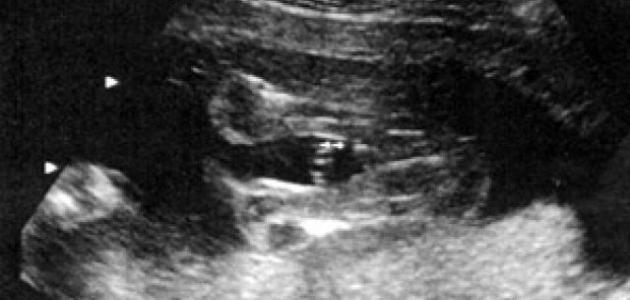

السونار هو جهاز تصوير يعمل بالموجات ما فوق الصوتية؛ حيث يرسل موجات صوتية بتردّدات عالية عبر رحم المرأة، وترتدّ هذه الموجات عن الجنين، ليتحول هذا الارتداد إلى صورة تظهر على الشاشة تُبيّن حركات، ووضعية الجنين في بطن أمه، وتنعكس هذه الموجات عن الأنسجة الصلبة كالعظام، وتظهر في الصورة بلونٍ أبيض، وتنعكس أيضاً على الأنسجة الناعمة وتظهر باللون الرمادي، أما السوائل كالسائل الأمنيوسي الذي يحيط بالجنين يظهر باللون الأسود، والهدف من استخدام هذا الجهاز هو معرفة إن كان الجنين ينمو بشكل طبيعي أم لا.

معرفة جنس الجنين وهو في رحم المرأة ممكن، ولكن لو كان الطفل في وضعية خاطئة؛ فقد يكون ذلك صعباً، وفي حال كان الجهاز متطوراً فتحديد جنس الجنين ممكن خلال الشهر الثالث من الحمل، أما الأجهزة العادية فلا يظهر ذلك إلّا بالشهر الخامس؛ لأنّ أعضاء الجنين الجنسية تكون قد اكتملت، وبرزت بشكل ملحوظ.

يُمكن تحديد جنس المولود من خلال ملاحظة شكل الأعضاء التناسلية؛ فإن كان جنس الجنين أنثى تظهر ثلاثة خطوط بيضاء على الشاشة وهي عبارة عن فتحة الفرج، والشفرين اللذين ينموان لاحقاً بعد البلوغ ليغطيا الفتحة، أما لو كان جنس الجنين ذكراً فسيكون العضو الذكري (القضيب) ظاهراً بوضوح، وإذا لم يكن واضحاً، فستظهر كرتان وهما الخصيتان بدلاً من الخطوط البيضاء؛ حيث تظهر الأعضاء التناسلية الذكرية بشكل السلحفاة. هناك مقولة خاطئة تقول إنّه عندما يظهر العضو الذكري يكون الجنين ذكراً، أما إذا لم يظهر شيء يكون الجنس أنثى.